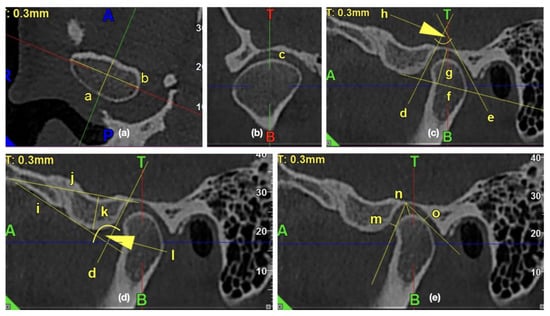

All the measurements were performed with the use of iRYS Softwarwe version 6.2. The primary outcome was the assessment of the impact of the osteoarthritic changes on the temporomandibular joint’s morphology. The 0.3-mm thickness axial slice of the condyle, in which the condyle had the maximum mediolateral dimension, was selected for further measurements. The sagittal axis was established as a line, which was perpendicular to and, at the same time, crossing the middle of the line connecting the mesial and distal end of the condyle. The obtained sagittal and coronal images were further examined and measured. Figure 2 presents the exemplary lines, points, and angles in the TMJ CBCT scans used for measurements.

Figure 2. The exemplary lines, points, and angles in the temporomandibular joints (TMJ) cone beam computed tomography (CBCT) scans used for measurements. (a) Morphology of mandibular condyle in the axial view: /a/condylar A-P dimension, /b/condylar width; (b) Shape of condyle head in the coronal view: /c/condyle’s superior surface view assessment; (c) Morphology of glenoid fossa in the sagittal view: /d/PE line, /e/AT line, /f/glenoid fossa basal line, /g/glenoid fossa depth, /h/glenoid fossa divergence angle; (d) Morphology of articular eminence in the sagittal view: /i/AE line, /j/eminence basal line, /k/articular eminence height, /l/articular eminence divergence angle; (e) Assessment of anterior, posterior, and superior joint spaces in the sagittal view: /m/anterior joint space, /n/superior joint space, /o/posterior joint space.